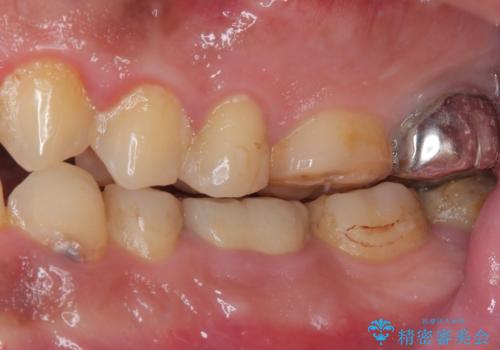

- 奥歯の歯肉から定期的に膿が出てくるとのことで来院された患者様です。

レントゲン写真などの診察を行った結果、根管治療が必要であったため、現在のクラウンを除去し、根管治療を行うこととしました。

根管治療後は症状を確認し、速やかにオールセラミッククラウンにて補綴治療を行うこととしました。

病変が消退しているかどうか、半年、1年とレントゲン写真で経過観察を行う必要があります。

4ヶ月後のレントゲンでは、病変の消退が認められました。